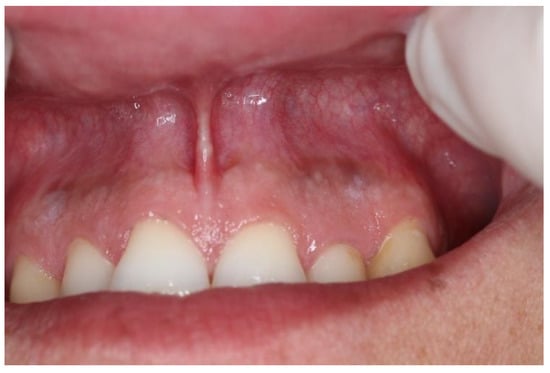

| Snus | 5–10 | 5–10 | White, linear lesions (Figure 4) | Right upper vestibule |